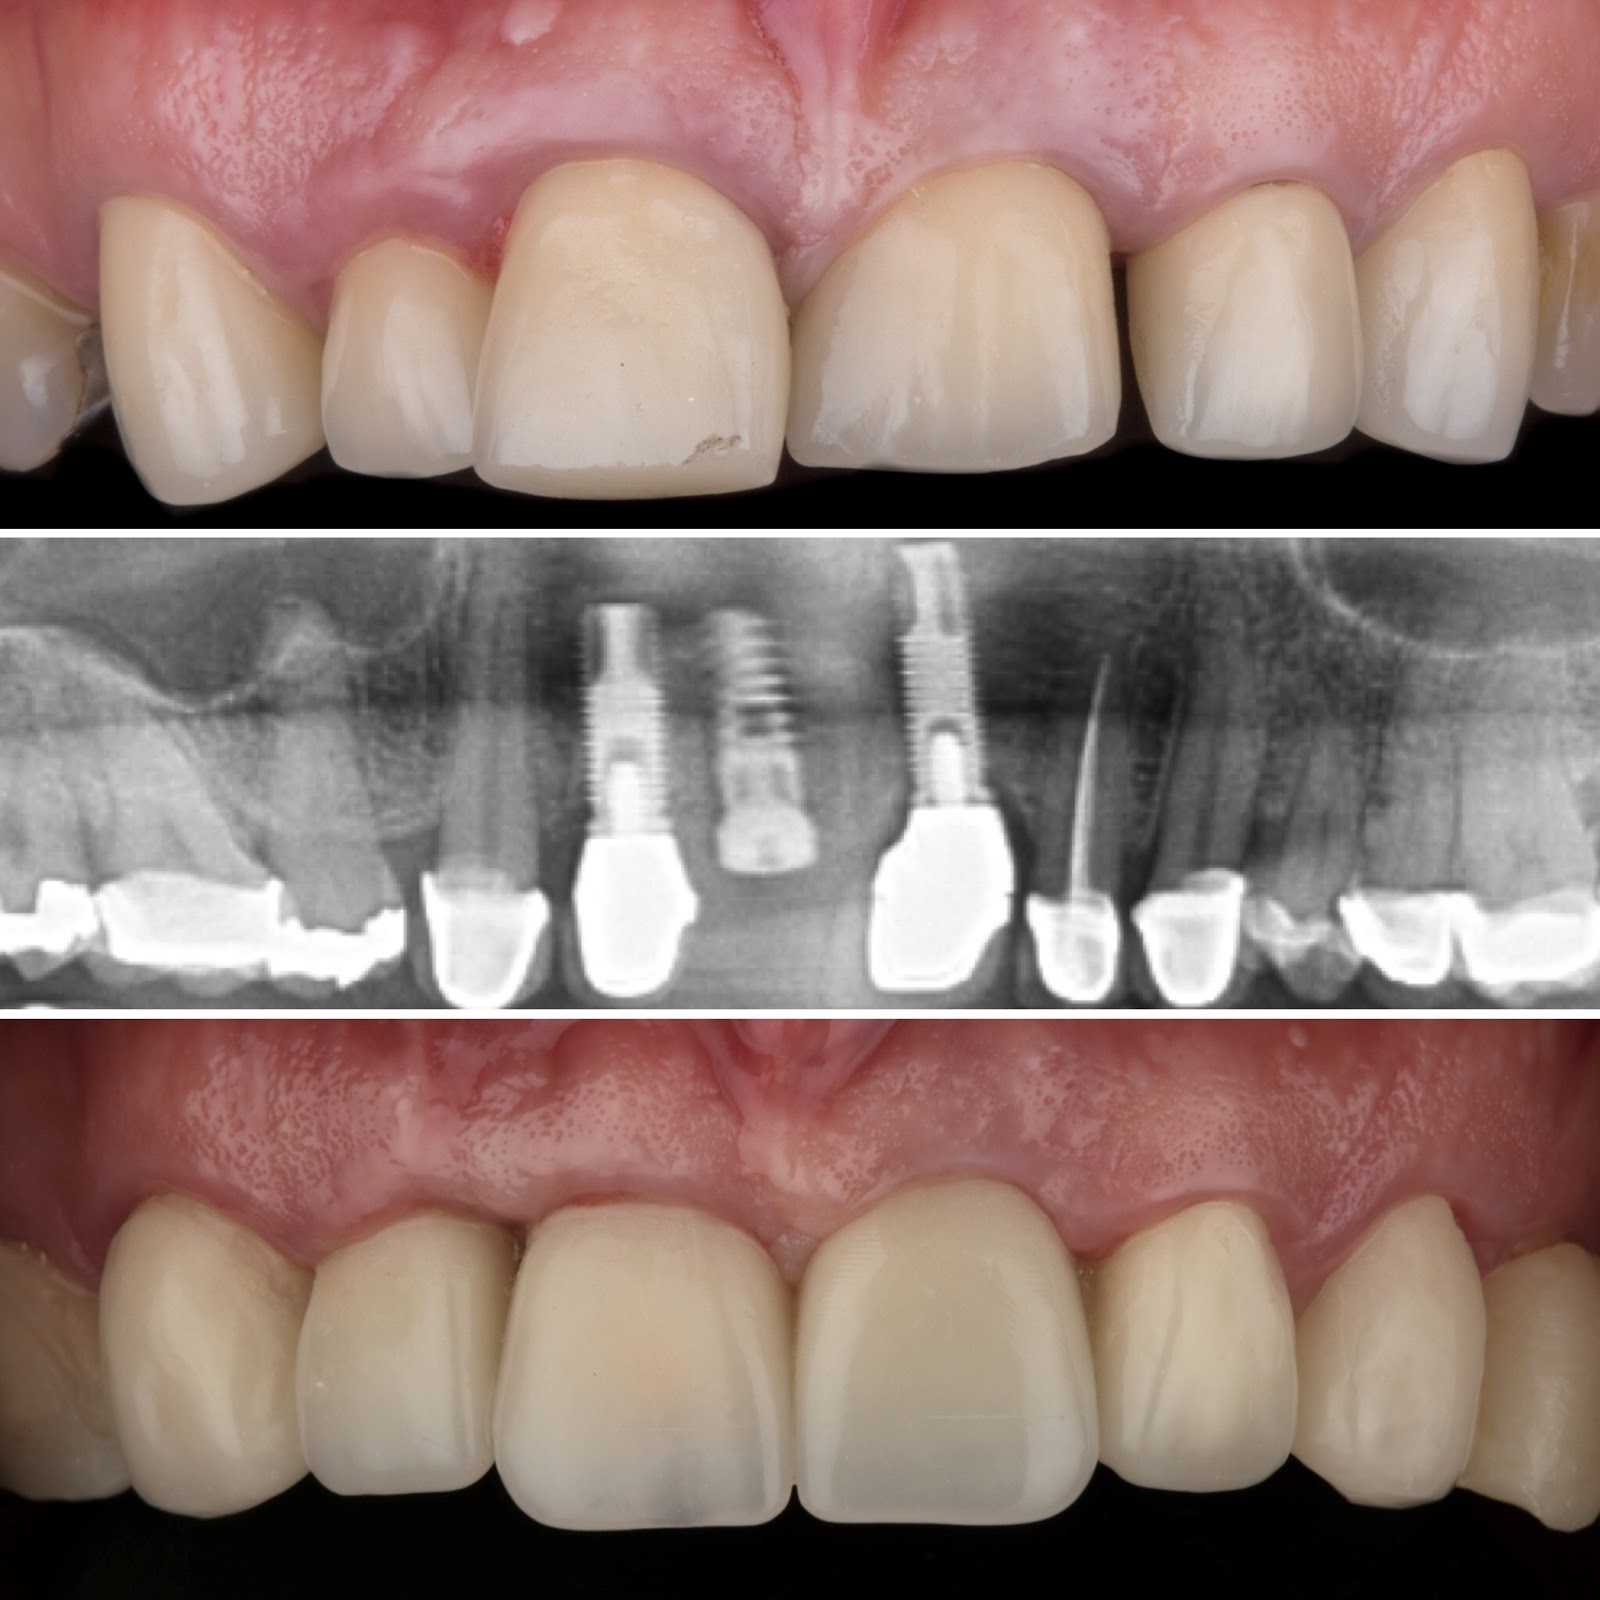

Dr. Ricardo Velázquez García es un dentista destacado en Colima, especializado en implantes dentales y cuidado integral de la salud bucal. Ubicado en el Centro Médico Puerta de Hierro, en Calle Ignacio Sandoval 1699-Consultorio 312, Girasoles, ofrece un ambiente profesional y acogedor para todos sus pacientes. Con una sólida reputación respaldada por una calificación de 5 estrellas basada en 235 opiniones, el Dr. Velázquez se distingue por su atención personalizada y la calidad de sus tratamientos. Sus pacientes valoran especialmente la amabilidad del equipo, la limpieza profunda y los resultados efectivos, como blanqueamientos dentales y procedimientos de bonding. La clínica cuenta con tecnología avanzada y un equipo comprometido en brindar una experiencia cómoda y segura. Para agendar una cita o solicitar información, puede comunicarse al teléfono 312 688 2357 o visitar su sitio web oficial https://dentaldesign.acecli.cloud/. El Dr. Ricardo Velázquez García es una opción confiable para quienes buscan mejorar su sonrisa y mantener una salud dental óptima en Colima.

Dr. Ricardo Velazquez García is a highly regarded dentist in Colima, specializing in dental implants and comprehensive oral health care. Located at Centro Medico Puerta de Hierro, Calle Ignacio Sandoval 1699-Consultorio 312, Girasoles, the clinic provides a professional and welcoming environment for all patients. With a 5-star Google rating from 235 reviews, Dr. Velazquez is known for his personalized approach and high-quality dental treatments. Patients appreciate the friendly and professional staff, thorough cleanings, and effective results including teeth whitening and bonding procedures. The clinic is equipped with advanced technology and a team dedicated to delivering a comfortable and safe experience. To schedule an appointment or request more information, contact the office at 312 688 2357 or visit the official website at https://dentaldesign.acecli.cloud/. Dr. Ricardo Velazquez García is a trusted choice for those seeking to improve their smile and maintain excellent dental health in Colima.